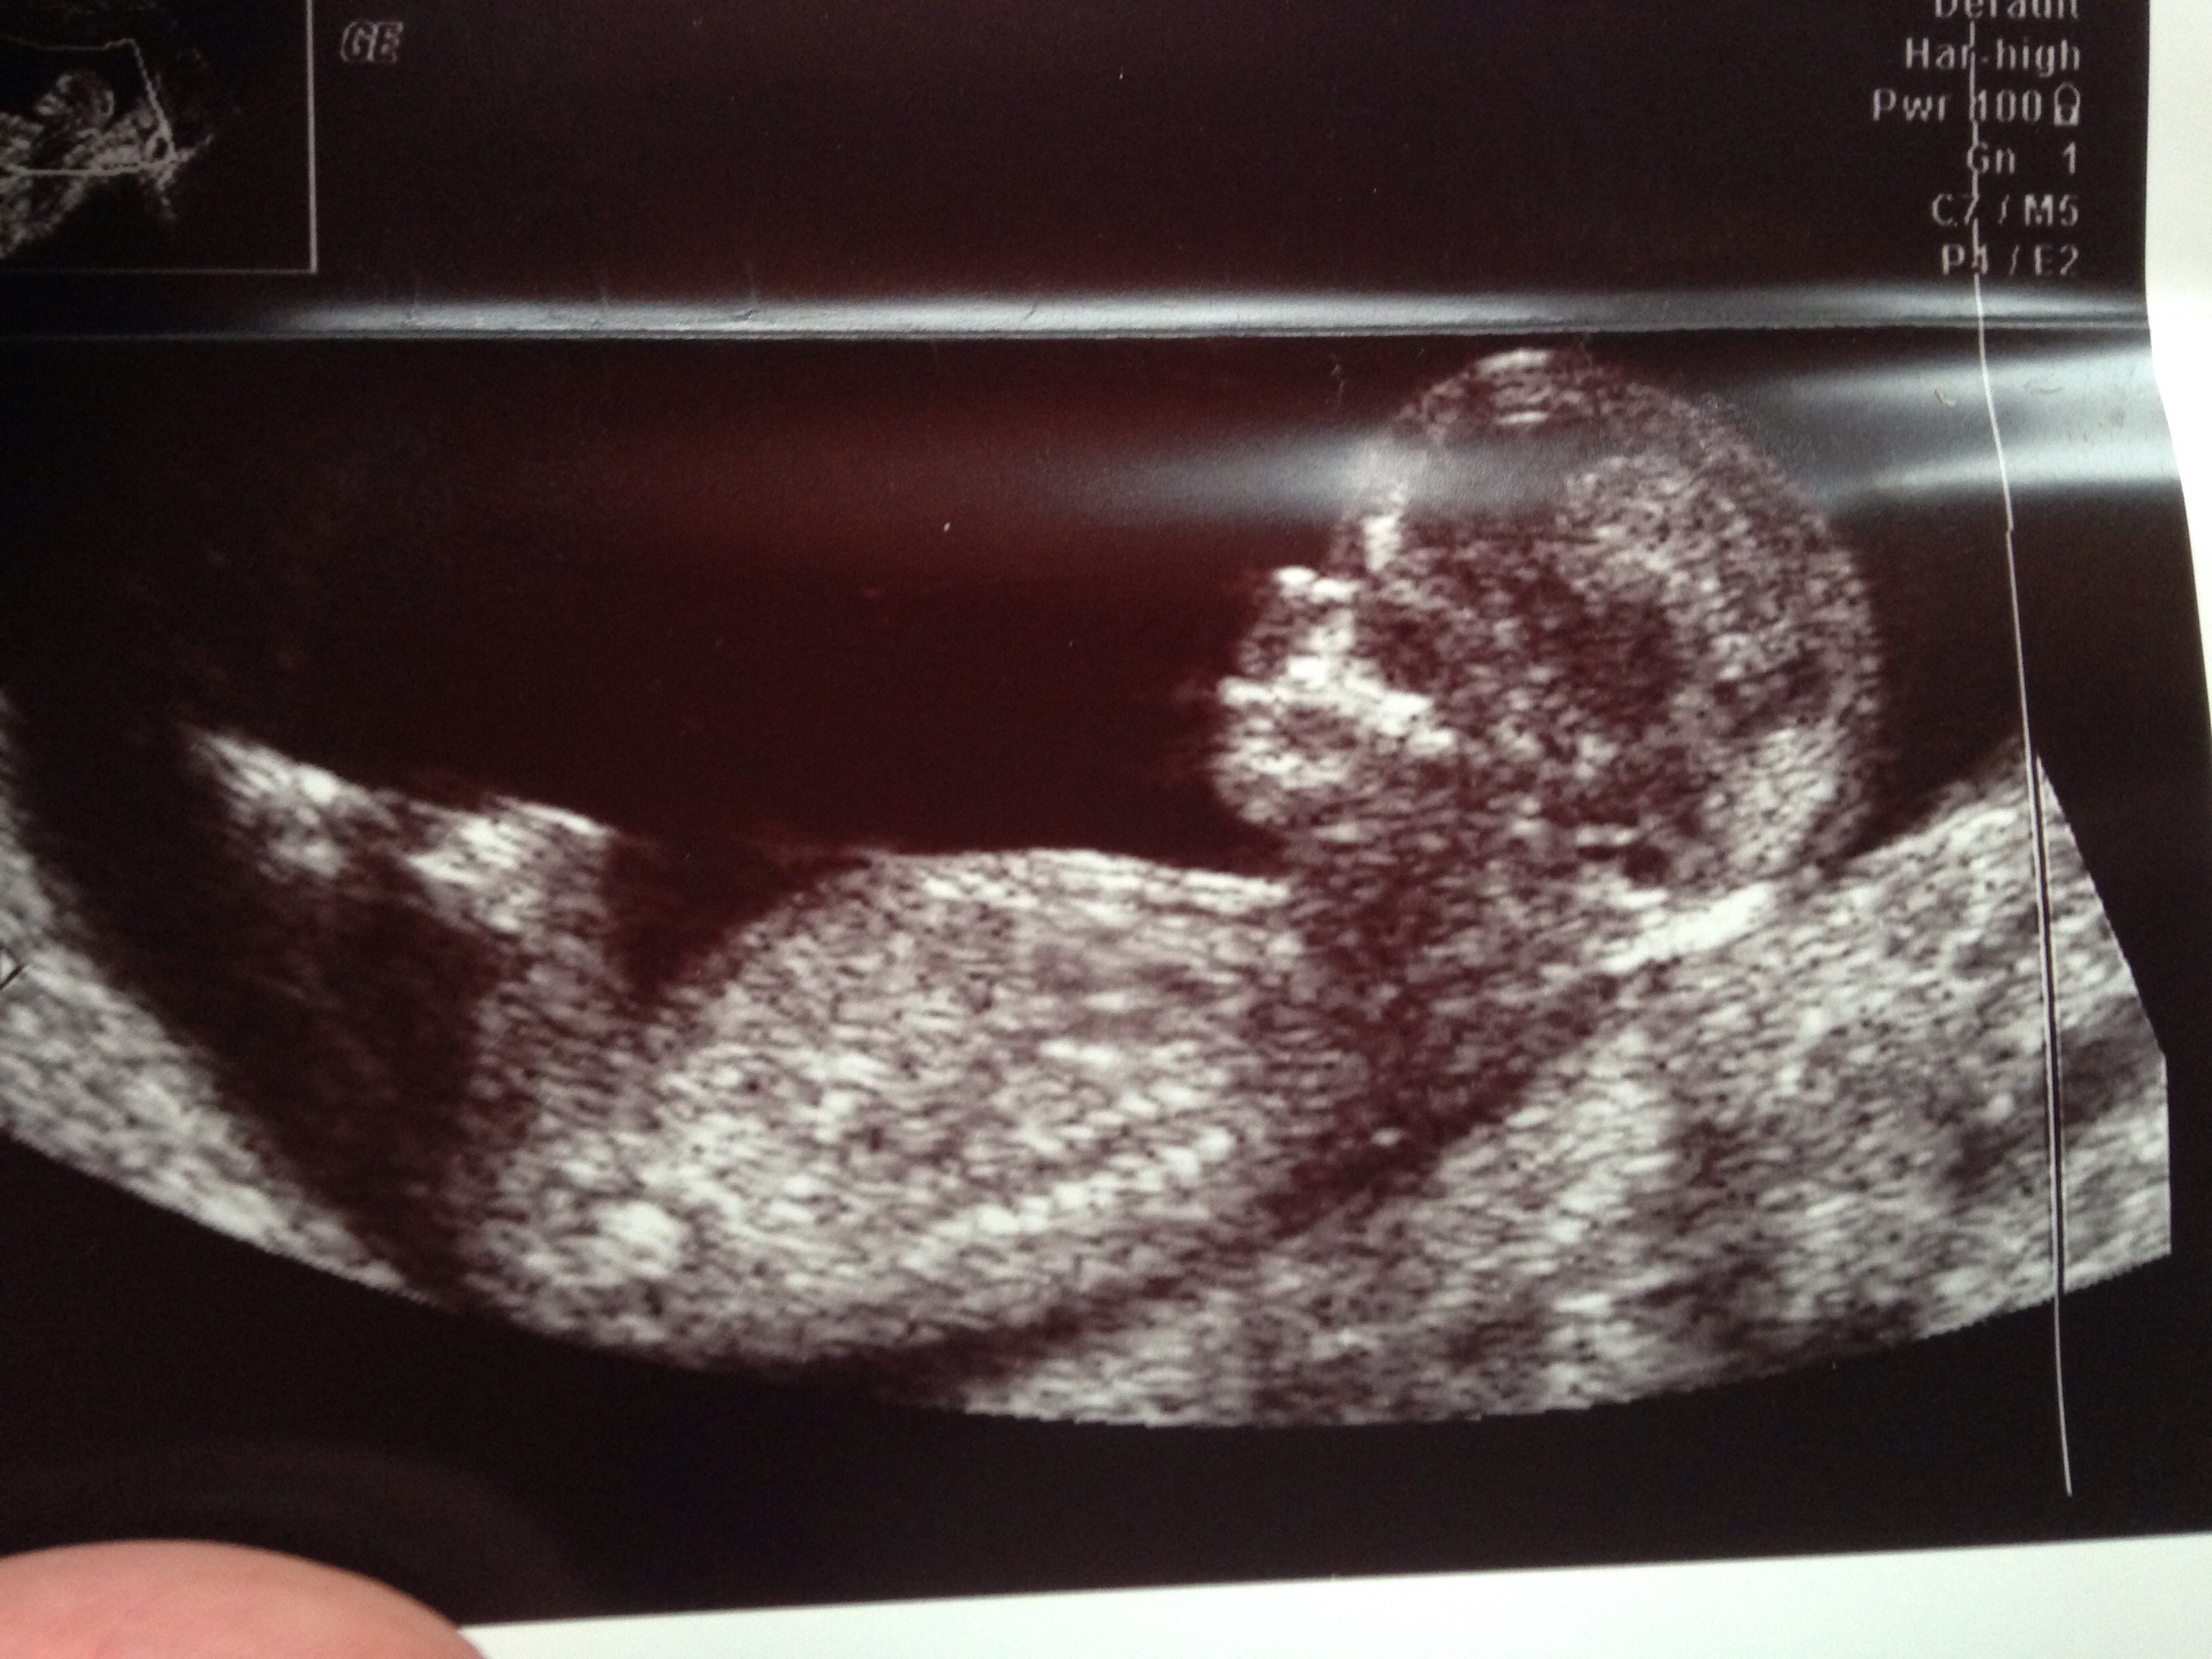

gestation is 13wks - please tell me what you all think?

I would guess boy too; the angle isn't particularly great however the nub is very obvious for 13 weeks. Good luck to her! :) xx

I thought girl from first nub pic. But last nub pic looks more angled up- boyish